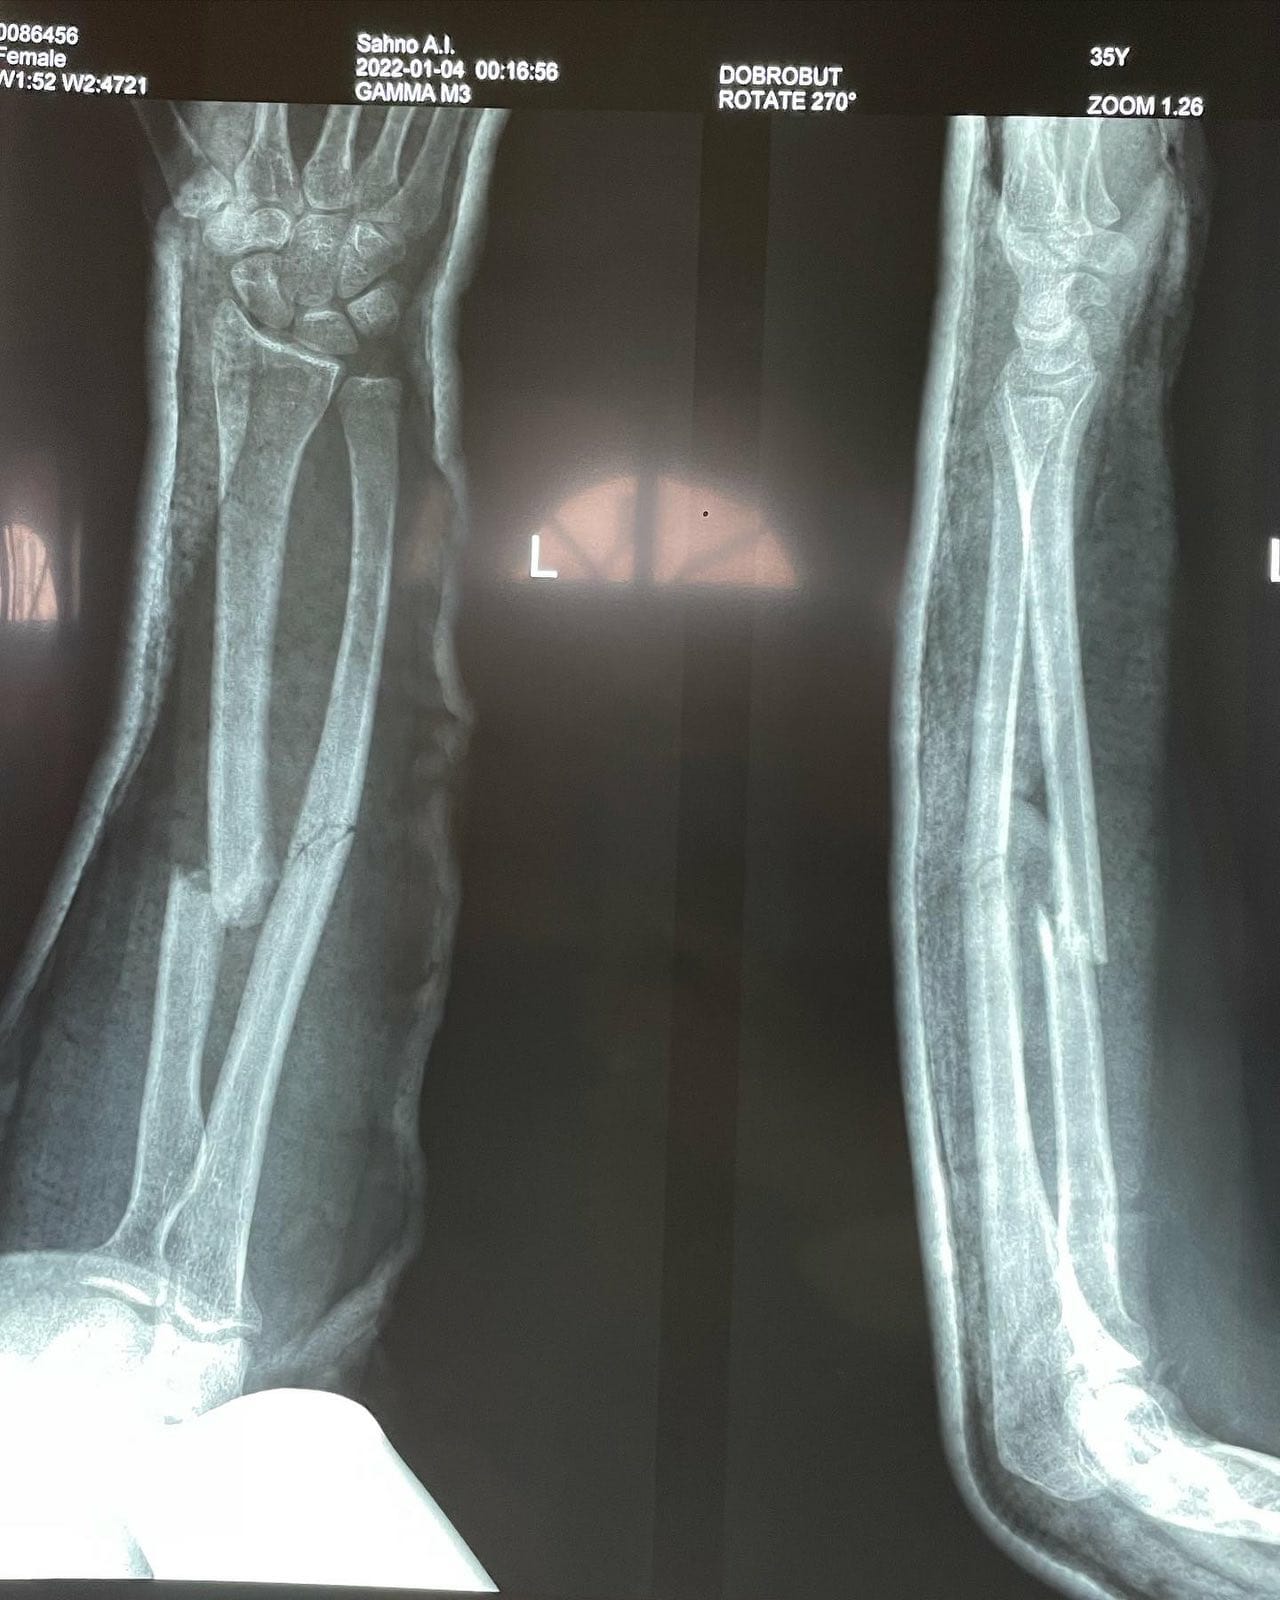

Коррекция при переломах костей после травм